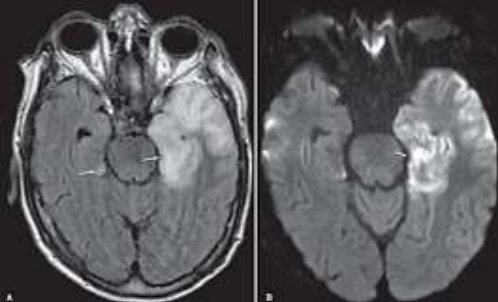

Paciente de 8 anos, com histórico de febre, cefaléia, crises convulsivas reentrantes e rápida progressão para rebaixamento do nível de consciência. Realizada punção lombar que demonstrou celularidade elevada com predomínio de linfócitos com glicose e proteínas normais. Realizou ressonância magnética do crânio que demonstrou os achados abaixo.